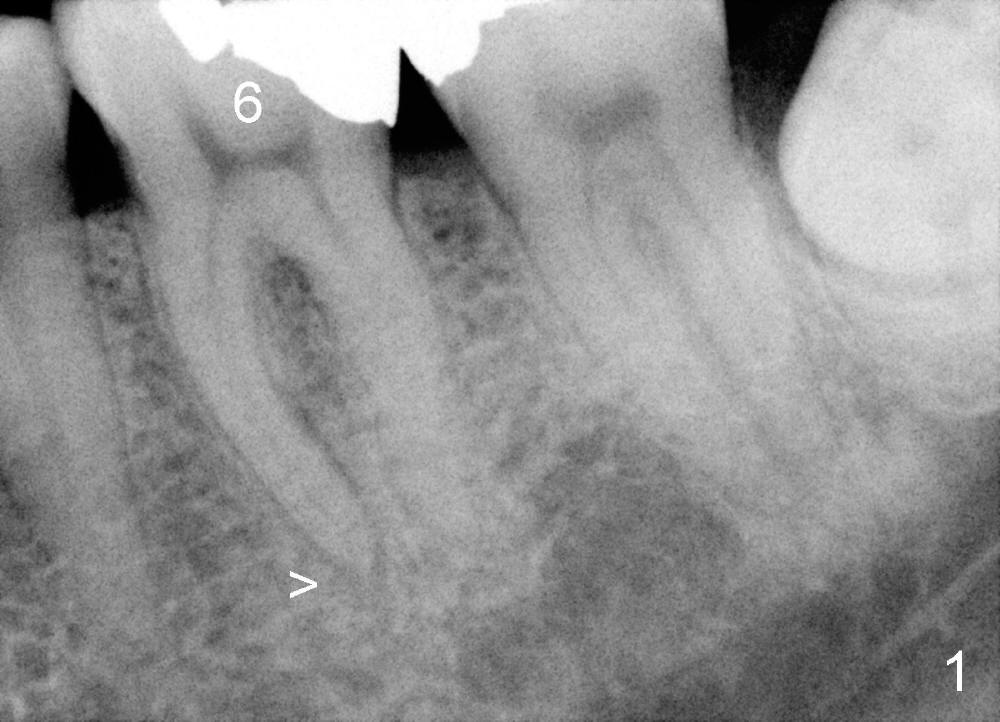

其实本文题目是如何让植牙病人找上门。冯女士四十二岁,四五年前因左下六牙痛第一次登门就诊,X光片显示牙根很长(图一),近中根根尖有阴影(>),那根牙根弯曲,总之,稀里糊涂开始根管治疗,结果有四根根管(图二),又长又弯,远中舌侧根断针(>),但是重新通过,辛辛苦苦完成根管治疗时才发现远中舌侧根弯弯曲曲(图三箭头,黑色箭头指向原来断针)。这些年来这颗牙齿没问题,但是左上七号牙老是发炎,全景片表明那颗牙齿根分叉处有阴影(图四箭头),一直劝她拔牙,植牙,上个月她终于同意拔牙,准备年底植牙。只有认认真真为病人解决痛苦,才能赢得他们信任,一旦他们需要进一步治疗,也会乐意开口。根管治疗做起来吃力,但是最能显示赤胆忠心。做好根管治疗是开展植牙第一步,愿意保留牙齿的人,视牙如金,如果我们尽力而保留不了,他们还是愿意更上一层楼;轻易拔牙的病人很少后来回来做植牙。